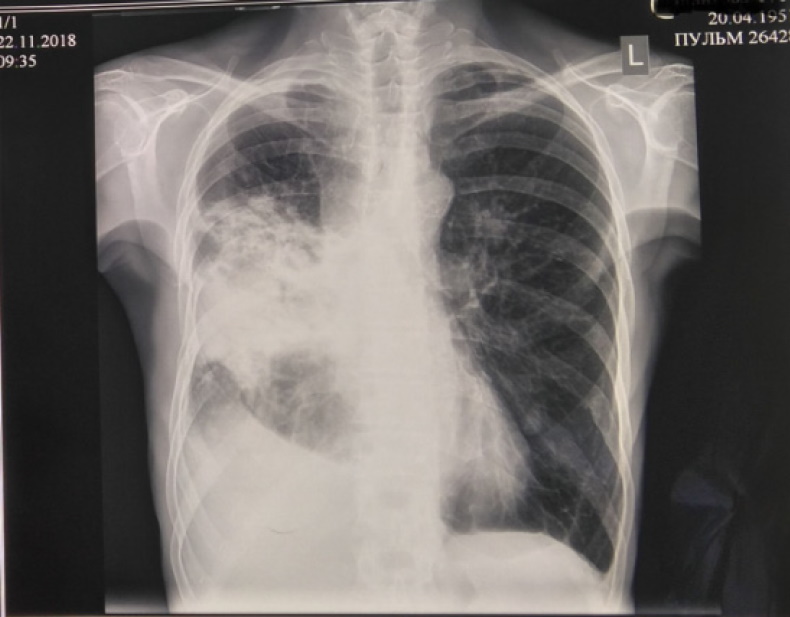

Рентгенограмма ОГК (после пункции) от 22.11.2018 г.: улучшение прозрачности легочной ткани в области верхушки и уменьшения количества жидкости до 6-го ребра справа, на остальном участке сохраняется субтотальное интенсивное затемнение за счет ателектаза средней и нижней долей. Слева легкое без инфильтративных изменений, в проекции «головки» корня легкого плотная очаговая тень 10×15 мм с довольно четким контуром. Легочный рисунок деформирован за счет явлений пневмосклероза. Средостение смещено вправо, тень сердца в пределах возрастной нормы (рис. 5).

Рис. 5. Рентгенограмма органов грудной клетки от 22.11.2018